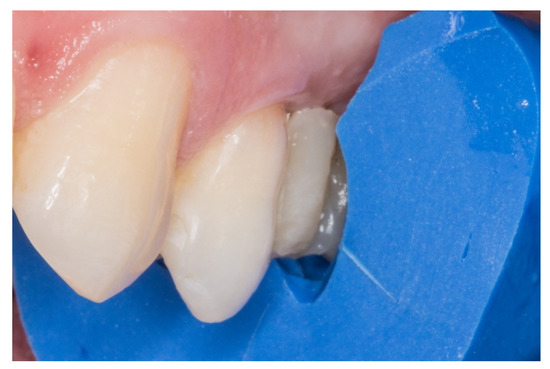

Figure 2.

The proximal faces of the adjacent teeth delimiting the edentulous space carved up to the level of the ideal point of contact (inlay cavities).

2. The proximal faces of the adjacent teeth delimiting the edentulous space were carved up to the level of the ideal point of contact (inlay cavities), to position the future horizontal structure of the fiberglass bridge (Figure 2).